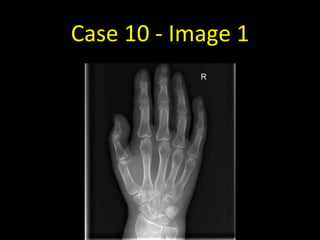

Case 10 - Image 1

Case 10

• Fracture of the distal radius

• Always remember to look

at the edge of the film!